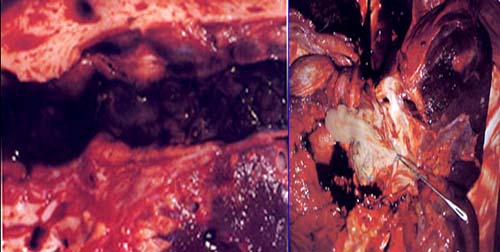

à chuyển viện vào TP. Hồ Chí Minh, tại đây bệnh nhân được nội soi mật tụy ngược dòng (thủ thuật ERCP) lấy 12 xác con SLGL, trong đó một số đã bị mụn nát và một ít sỏibùn ra theo, sau 5 ngày xuất viện về lại Quy Nhơn;

Trong ca bệnh chúng tôi báo cáo ở đây, sán đã di chuyển và gây nhiều ổ abces ở vị trí lách, gan và khu vực đầu tụy, ống mật chủ làm cho nhiều thầy thuốc chẩn đoán ban đầu rất khác nhau (lao hoặc di căn của ung thư tiêu hóa). Phản ứng tăng bạch cầu ái toan thể hiện và chỉ điểm viêm đáp ứng của một bệnh lý ký sinh trùng nhưng vẫn chưa được nhân ra ngay từ đầu. Phần lớn trường hợp, chẩn đoán khó khăn cả giai đoạn cấp và mạn tính, một vài ca bệnh như abces gan và khối di căn không phải dễ dàng để phân biệt.

Ca bệnh trình bày ở đây có tràn dịch có lẽ chỉ là “phản ứng” do viêm abces gan (P) mà lên. Sự di chuyển của sán đến lách và tụy được xác định qua CT-scanner. Xét nghiệm bệnh học xác định các vị trí tổn thương lạc chỗ lại chưa được làm, song sự cải thiện các tổn thương qua theo dõi điều trị là có giá trị khẳng định. Các bệnh nhân có tình trạng miễn dịch suy giảm (như trong trường hợ này là bệnh nhân đang bị lao) sẽ liên quan đến việc sử dụng thuốc lâu dài, có thể giải thích phần nào hiện tượng mà SLGL nhiễm vào và lan tỏa đến nhiều cơ quan như trong một số bệnh nhiễm trùng khác.